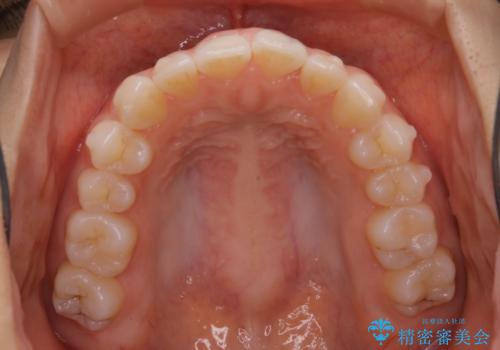

前歯のがたつきをインビザラインで治療

- 上下前歯のがたつきが気になるとの事で来院された患者様です。がたつきの程度が軽度であったため、インビザラインライトにて治療をおこないました。

がたつきの程度が軽度であったことと、インビザラインを正しく装着して頂けたことで短期間で治療終了することが出来ました。